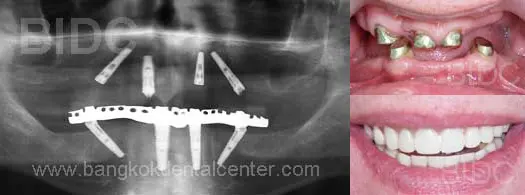

All-on-4 Case Done at BIDC

All on 4

All-on-4 Immediate Function

Diagnoses: Multiple Missing Upper and Lower teeth with bone loss

Treatment : All-on-4 implants with fixed hybrid bridge on full upper and lower arch, immediate function implants without bonegrafts

Patient Country : Netherlands